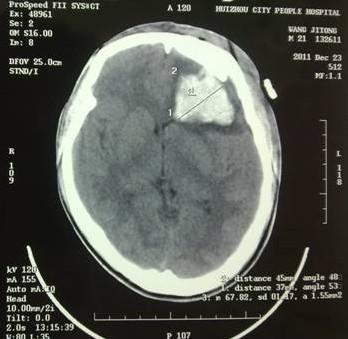

于是家屬慕名求助于我院余永強(qiáng)主任,在傷后第三天轉(zhuǎn)來我院。余永強(qiáng)主任主持術(shù)前討論,決定為患者施行微創(chuàng)手術(shù)清除血腫。通過CT掃描進(jìn)行術(shù)前精確定位,隨后在局麻下進(jìn)行微創(chuàng)手術(shù)。術(shù)中利用余主任設(shè)計(jì)研制的“e形微創(chuàng)手術(shù)定向儀”作引導(dǎo),將穿刺針準(zhǔn)確無誤置入血腫靶心,順利地清除了絕大部分血腫。術(shù)后復(fù)查頭顱CT,血腫清除超過90%(圖2)。憑借微創(chuàng)技術(shù),頭皮僅僅只需要一個(gè)直徑3毫米的小孔,通過一根高科技微創(chuàng)穿刺針,便可達(dá)到同樣的甚至更好的治療效果(圖3)。術(shù)后留置引流1天,第7天即痊愈出院。手術(shù)達(dá)到近乎“完美”的效果!患者親屬大為感慨微創(chuàng)手術(shù)的“神奇”,術(shù)后專程送來錦旗一幅――“微創(chuàng)手術(shù)顯神功” ?。▓D4)

圖2(1):術(shù)后立即復(fù)查CT,血腫清除90%以上,穿刺針定位精確,

無損傷出血;

圖2(2):術(shù)后2周復(fù)查,腦組織恢復(fù)良好。